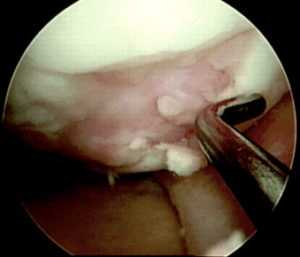

Схематичное изображение мозаичной пластики.